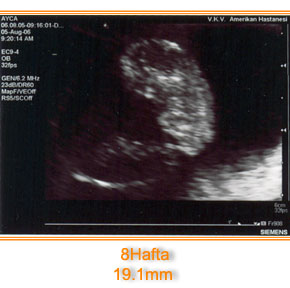

Bu çocuk hareket ediyor, kafasını kollarını hareket ettiriyor..!!

Benim hissettiğim sadece gülmek oldu çünkü annem baktı baktı ekrana ve ilk söylediği şey :

“Alpay bunun kafası sana benziyor”

yani şimdi Alpaya uzaylı kafalı mı demek istedi ne demek istedi anlamadım ki ..:) heyecanlandı ananaaanesiiiii….ve sallamış olduğu kafasını kendisine selam vermek olarak algılayan canım annem benim:)